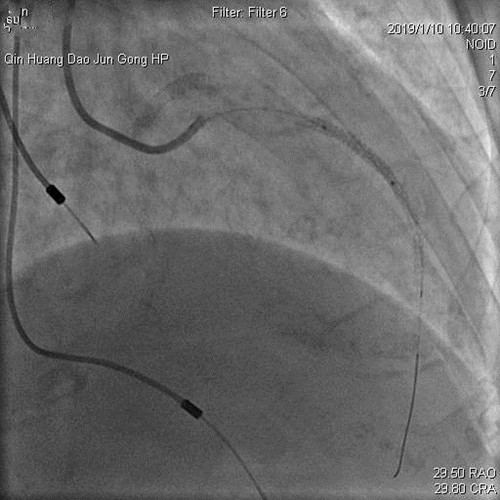

2019年1月10日,心内科王春梅主任、王嘉玮主治医师与北京安贞医院李昭教授共同完成首例冠脉支架内再狭窄药物球囊扩张术。手术的成功,对心内科介入手术的开展和医疗技术的提升具有重要意义。

患者杨某,女,74岁,因发作性胸闷到军工医院就诊。患者曾先后在某医院经冠脉植入过4枚支架及心脏永久起搏器,但是胸闷症状仍然没有解除。因杨某高龄、反复心梗、心衰,咨询多家医院均表示仅能药物保守治疗,拒绝为其行介入治疗。患者家属携带既往病历资料来军工医院咨询,心内科主任王春梅详细询问病情,积极与北京安贞医院李昭主任联系,详细查阅患者既往病历影像资料,考虑患者目前胸闷症状为前降支支架内再狭窄所致,有多次狭窄病变(病历资料显示狭窄病变为前降支两枚支架连接处的狭窄,既往因连接处狭窄已通过重叠植入支架治疗)。

王主任考虑患者高龄,反复心梗,心功能差,手术风险高,难度大。患者前降支血管承担着几乎整个心脏的供血,再狭窄部位为前降支的关键位置,如果手术过程稍有不慎,将会危及生命,后果将不堪设想。

经过反复沟通,向患者及家属详细讲解手术过程、风险及并发症。家属对军工医院表示信任,同意使用药物球囊治疗狭窄病变。经过近1小时的手术,成功为患者放入了药物球囊。出院2周后医生随访,张某病情平稳,无胸闷、胸痛症状。患者和家属对军工医院心内科王春梅主任勇于担当和技术精湛的医生团队表示感谢。